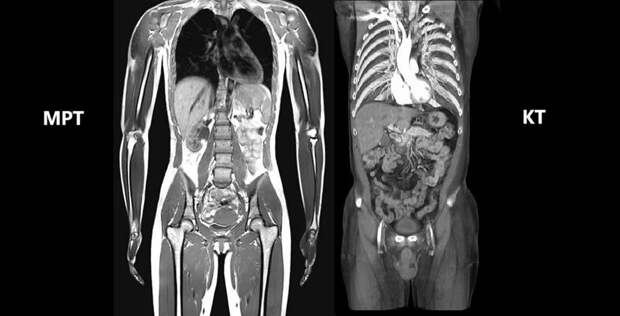

КТ или МРТ всего организма?

Выбор между обследованиями делает врач. Расскажем, чем он руководствуется при этом.

Это зависит от конкретной клинической ситуации, состояния больного. Компьютерная томография предпочтительнее для обследования патологий костей, легких, травм, внутренних кровотечений. Этот метод обеспечивает скорость исследования, визуализацию плотных структур. Оно назначается для выявления острых состояний: травм, сосудистых катастроф (тромбоэмболия). Минусом является ионизирующее излучение, ограничивающее возможность обследования определенных групп больных.

Магнитное исследование более информативно для мягких тканей, нервной системы, связок, сосудов. Оно проходит без применения радиации. Эффективно при диагностике опухолей, воспалительных процессов, заболеваний головного и спинного мозга. Занимает больше времени. Это неудобно для людей с клаустрофобией, неспособностью долго сохранять неподвижность. Процедура не подходит для пациентов с металлическими имплантатами, кардиостимуляторами, другими электронными устройствами.